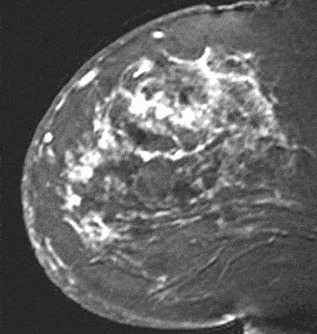

Internal enhancement of masses can be described as homogeneous or heterogeneous. Homogeneous enhancement is confluent and uniform (Fig. 8). Heterogeneous enhancement is non-uniform with areas of variable signal intensity (SI) (Fig. 9). Heterogeneous enhancement can be further classified as rim (Fig. 10), dark internal septations (Fig. 11), enhancing internal septations (Fig. 12) or central enhancement (Fig. 13).

Figure 10. Rim-enhancing mass. Pathology – Infiltrating ductal cancer.